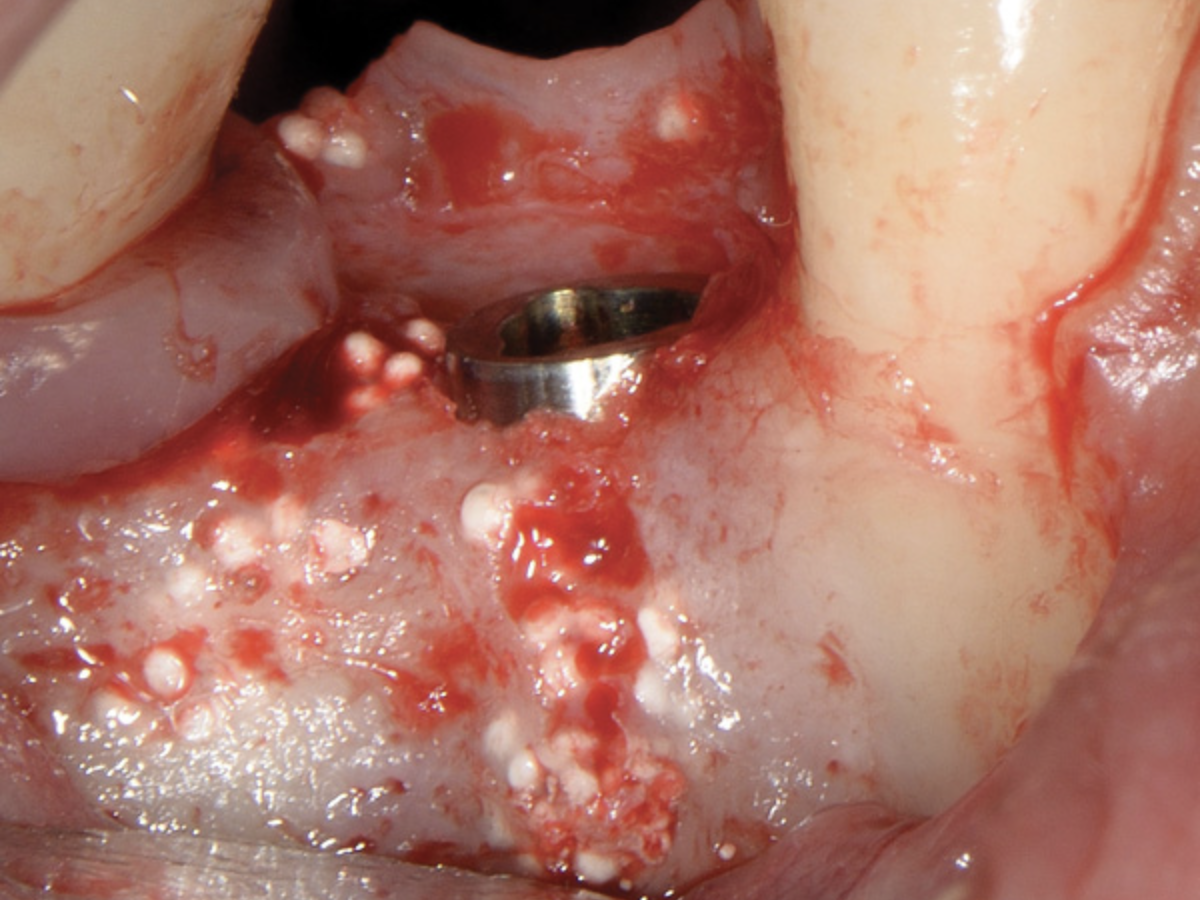

There are concerns that graft materials that fully resorb in a short timeframe may contribute to site collapse. Pure-phase beta-tricalcium phosphate (ß-TCP) (Figure 4) was one of the materials developed to address this concern. In a clinical and histologic study, extraction sockets were shown to have 91% of ridge width preserved when grafted with ß-TCP (Cerasorb®, Curasan, Inc., www.curasaninc.com) and covered with either a collagen or dense PTFE barrier.7 Dental implants were placed in these patients at 4 to 6 months postoperatively, a later time period than in the calcium sulfate studies. The patient shown in Figure 4 had only three maxillary teeth remaining, supporting an ill-fitting removable prosthesis. Due to the significant occlusal forces that were to be demanded on this single-tooth, implant-supported restoration, it was deemed advantageous to maximize the amount of vital bone in the recipient site. The area was left to heal for 7 months before flap exposure (Figure 5), implant placement in an ideal location, and graft analysis in the largest part of the defect. Analysis of the retrieved specimen showed 85% vital bone in the apical 90% of the core and a thin layer of nonresorbed ß-TCP at the crestal portion (Figure 6).

Fig 4. Pure-phase ß-TCP covered with a collagen barrier.

Figure 4

Fig 5. Reentry at 7 months demonstrated full ridge width preservation and minimal residual graft material.